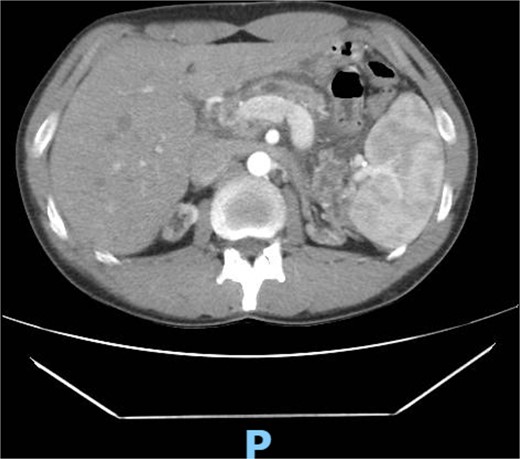

An abdominal ultrasound (Fig. 1), a computed tomography (Fig. 2) and a magnetic resonance cholangiopancreatography (MRCP) resonance showed diffuse dilation of the main pancreatic duct the duct of Santorini and the secondary ducts. Stones inside the main pancreatic duct in the head region, measuring approximately 1.1 cm. Reduction in the thickness of the pancreatic parenchyma, associated with small calcifications in between (Fig. 2).

Abdominal computed tomography shows a diffuse dilation of the main pancreatic duct and Santorini duct, as well as dilation of secondary ducts. There are stones in the main pancreatic duct in the head region. Also, there is a reduction in the thickness of the pancreatic parenchyma, associated with small intervening calcifications, possibly due to chronic pancreatitis.